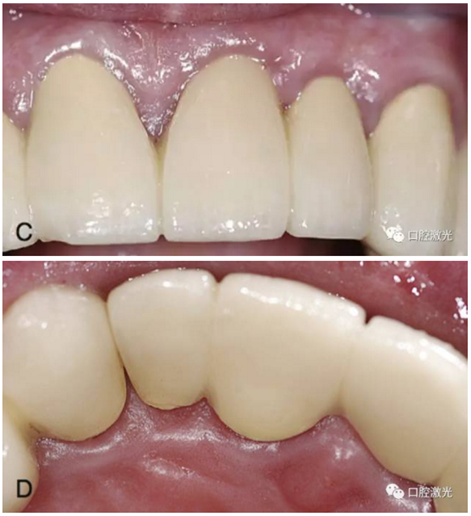

激光在牙冠延長術(shù)中的應(yīng)用

隨著美學(xué)修復(fù)和保存修復(fù)的不斷發(fā)展,牙冠延長術(shù)在臨床中的應(yīng)用越來越多。牙冠延長術(shù)的目的是在符合牙周生物學(xué)寬度條件下暴露更多的健康牙體組織。

口腔激光在固定修復(fù)中的應(yīng)用